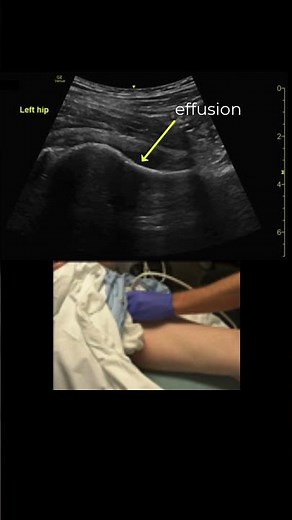

Hip Effusion, Diagnosis and Arthrocentesis #POCUS #emergencymedicine #orthopaedics

YouTube

Joseph Minardi

1.8K views

5 months ago